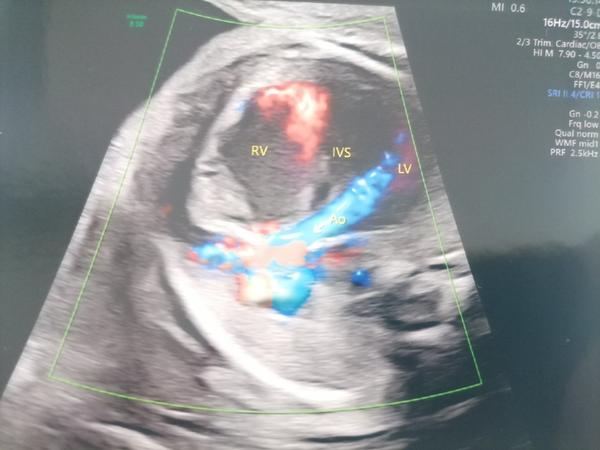

popísaný nález nie je typickým obrazom pre vrodenú chybu srdca u detí.

Doporučujem Vám objednať sa na kontrolné prenatálne vyšetrenie v Detskom kardiocentre ešte pred narodením dieťaťa s cieľom potvrdenia uvedenej diagnózy.